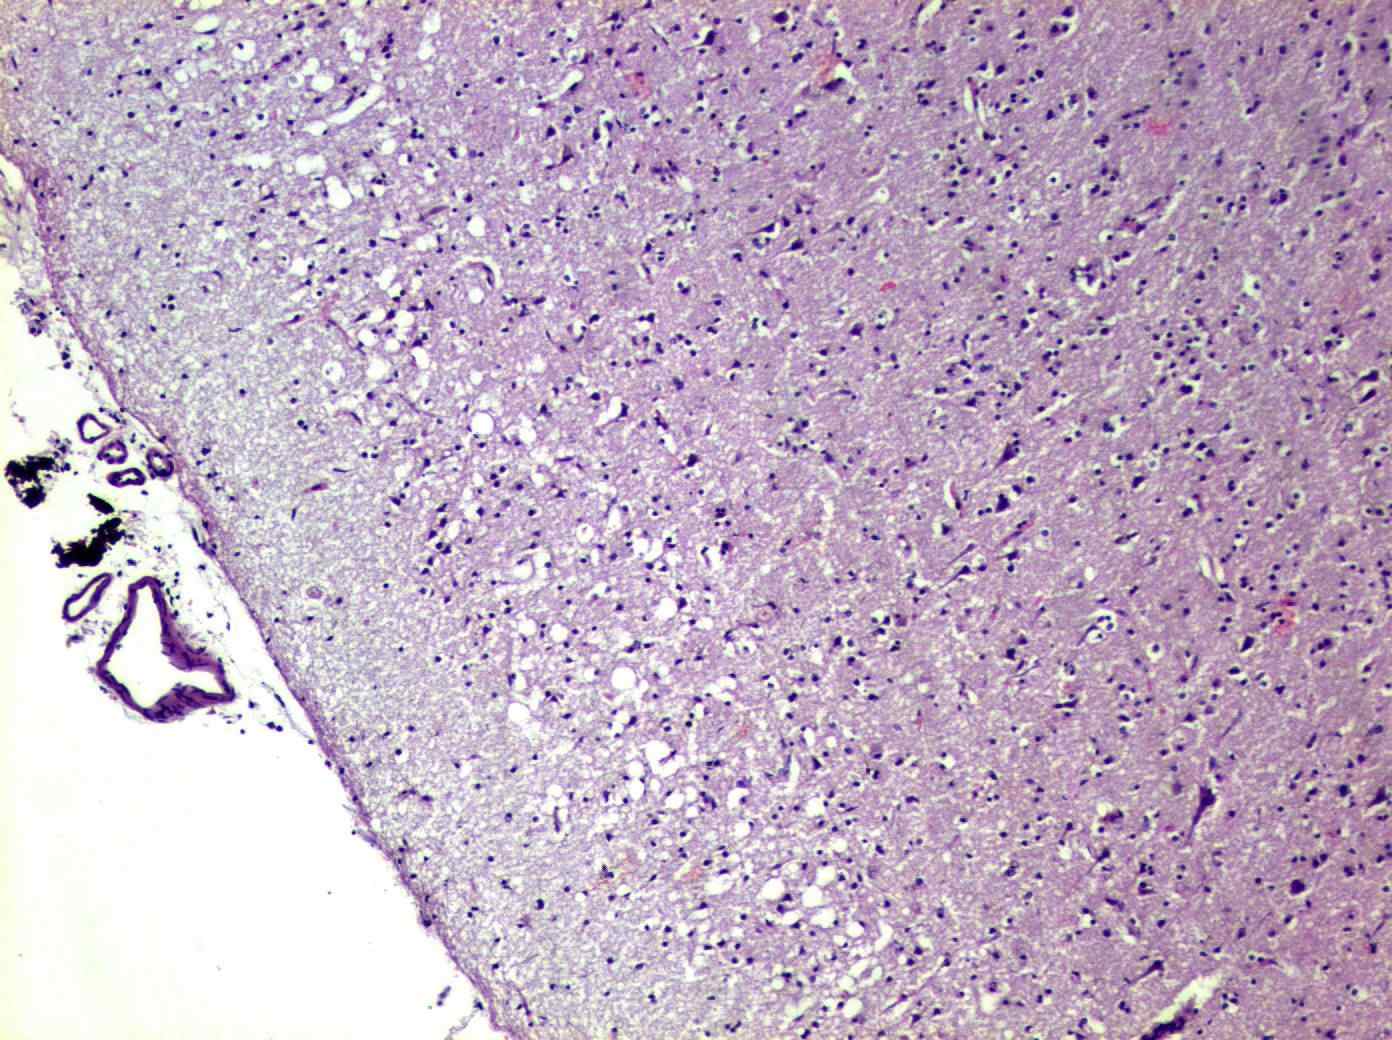

После кончины пациентки специалисты провели серию морфологических исследований. Мозговая ткань была обработана формалином для максимального сохранения структуры клеток, а затем окрашена с использованием специальных методик, чтобы выявить тау-белки и характерные изменения нейронов. В гистологическом анализе обнаружили ключевые признаки деменции Пика: значительная атрофия лобных и височных отделов мозга, наличие особых скоплений — телец Пика — в нейронах. Под микроскопом чётко определялись пустые нейроны с ядрами, смещёнными к периферии — классический маркёр патологии.